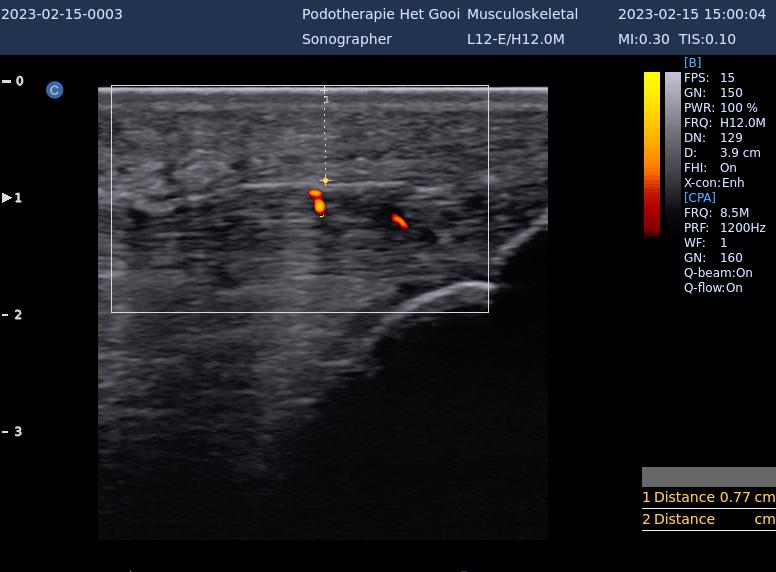

Infrapatellaire Insertietendopathie / Apexitis Patellae

Een van de meest voorkomende knieklachten bij sporters is de spingersknie, een overbelasting van de aanhechting van de kniepees aan de onderzijde van de knieschijf. Deze blessure treedt vooral op bij serve-, volleyspelers en handballers daar zij veel moeten sprinten en springen.

patella pees